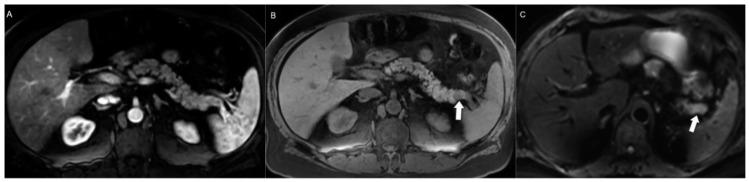

Neuroendocrine neoplasms (NENs) are a diverse group of tumors with varying clinical behaviors. Their incidence has risen due to increased awareness, improved diagnostics, and aging populations. The 2019 World Health Organization classification emphasizes integrating radiology and histopathology to characterize NENs and create personalized treatment plans. Imaging methods like CT, MRI, and PET/CT are crucial for detection, staging, treatment planning, and monitoring, but each of them poses different interpretative challenges and none are immune to pitfalls. Treatment options include surgery, targeted therapies, and chemotherapy, based on the tumor type, stage, and patient-specific factors. This review aims to provide insights into the latest developments and challenges in NEN imaging, diagnosis, and management.

神经内分泌肿瘤(NENs)是一组具有不同临床行为的肿瘤。由于认识的提高、诊断方法的改进和人口老龄化,其发病率有所上升。2019年世界卫生组织分类强调整合放射学和组织病理学以对NENs进行特征描述并制定个性化治疗方案。CT、MRI和PET/CT等成像方法对于检测、分期、治疗规划和监测至关重要,但每种方法都带来不同的解读挑战,且都难免存在缺陷。治疗选择包括手术、靶向治疗和化疗,具体取决于肿瘤类型、分期和患者特定因素。本综述旨在深入探讨NENs成像、诊断和管理方面的最新进展和挑战。